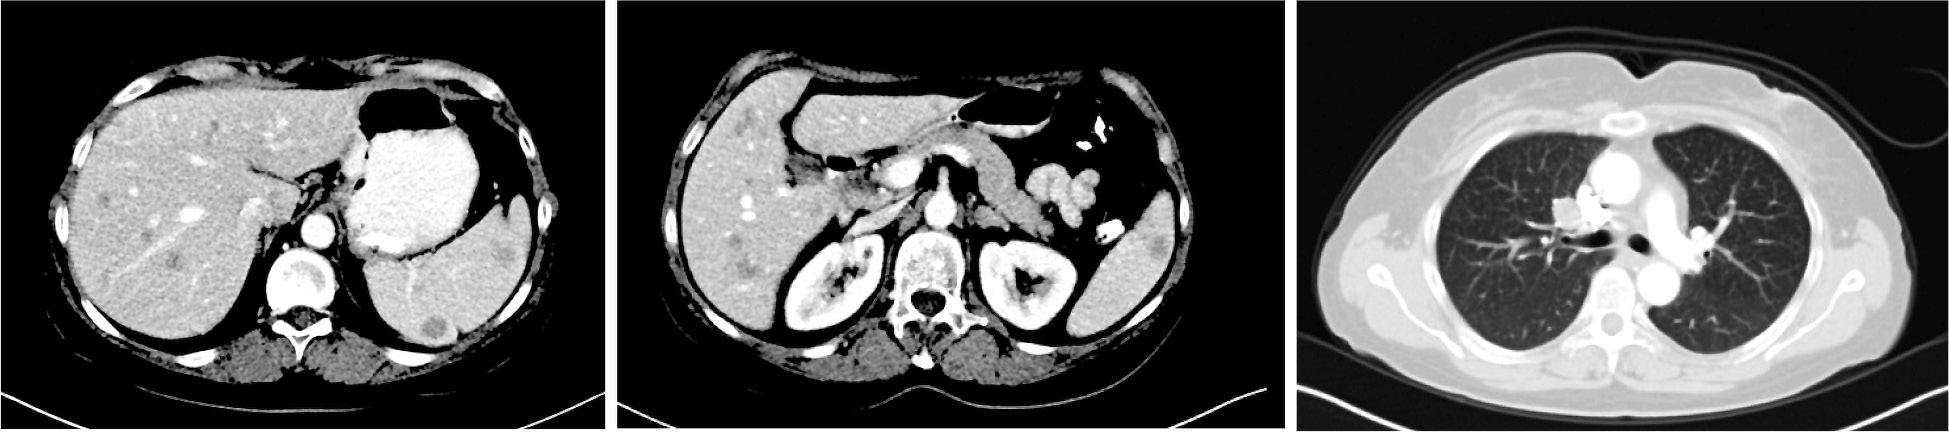

При обследовании (КТ органов грудной клетки, органов брюшной полости и таза с внутривенным контрастированием – в/в) подтверждено множественное метастатическое поражение печени, селезенки, лимфоузлов средостения, практически всех отделов костной системы (рис. 4, 5), при этом уровень ЛДГ оставался в норме, а общее состояние по шкале Восточной объединенной онкологической группы (Eastern Cooperative Oncology Group) соответствовало 1 за счет симптомов заболевания. Мтс в головном мозге по данным магнитно-резонансной томографии (МРТ) от 10.2015 не выявлены. При стадировании заболевания согласно Американскому объединенному онкологическому комитету (American Joint Committee on Cancer – AJCC) версии 7 – TxN0M1с, IV стадия; по AJCC версии 8 – TxN0M1с(0), IV стадия.

Рис. 4. КТ органов грудной клетки, органов брюшной полости и таза с в/в контрастированием от 10.2015.